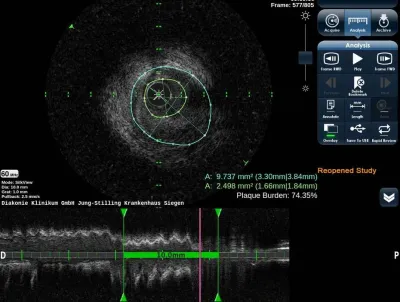

(Bildquelle: @Kodak Alaris)